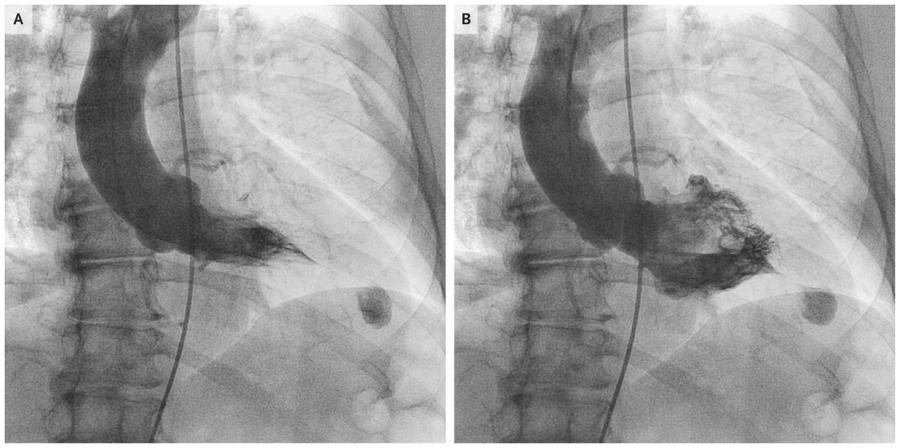

3. 左室造影:

对心尖肥厚型心肌病患者行右前斜30°左心室造影可见舒张期左心室呈特征性“黑桃样”形改变,心尖部心肌明显肥厚;

收缩期可见心尖腔部位完全闭塞。

似扑克牌“黑桃”形改变,尖部向右下

影像学检查见舒张期左心室呈特征性“黑桃样“,收缩期显著的心尖腔消失;